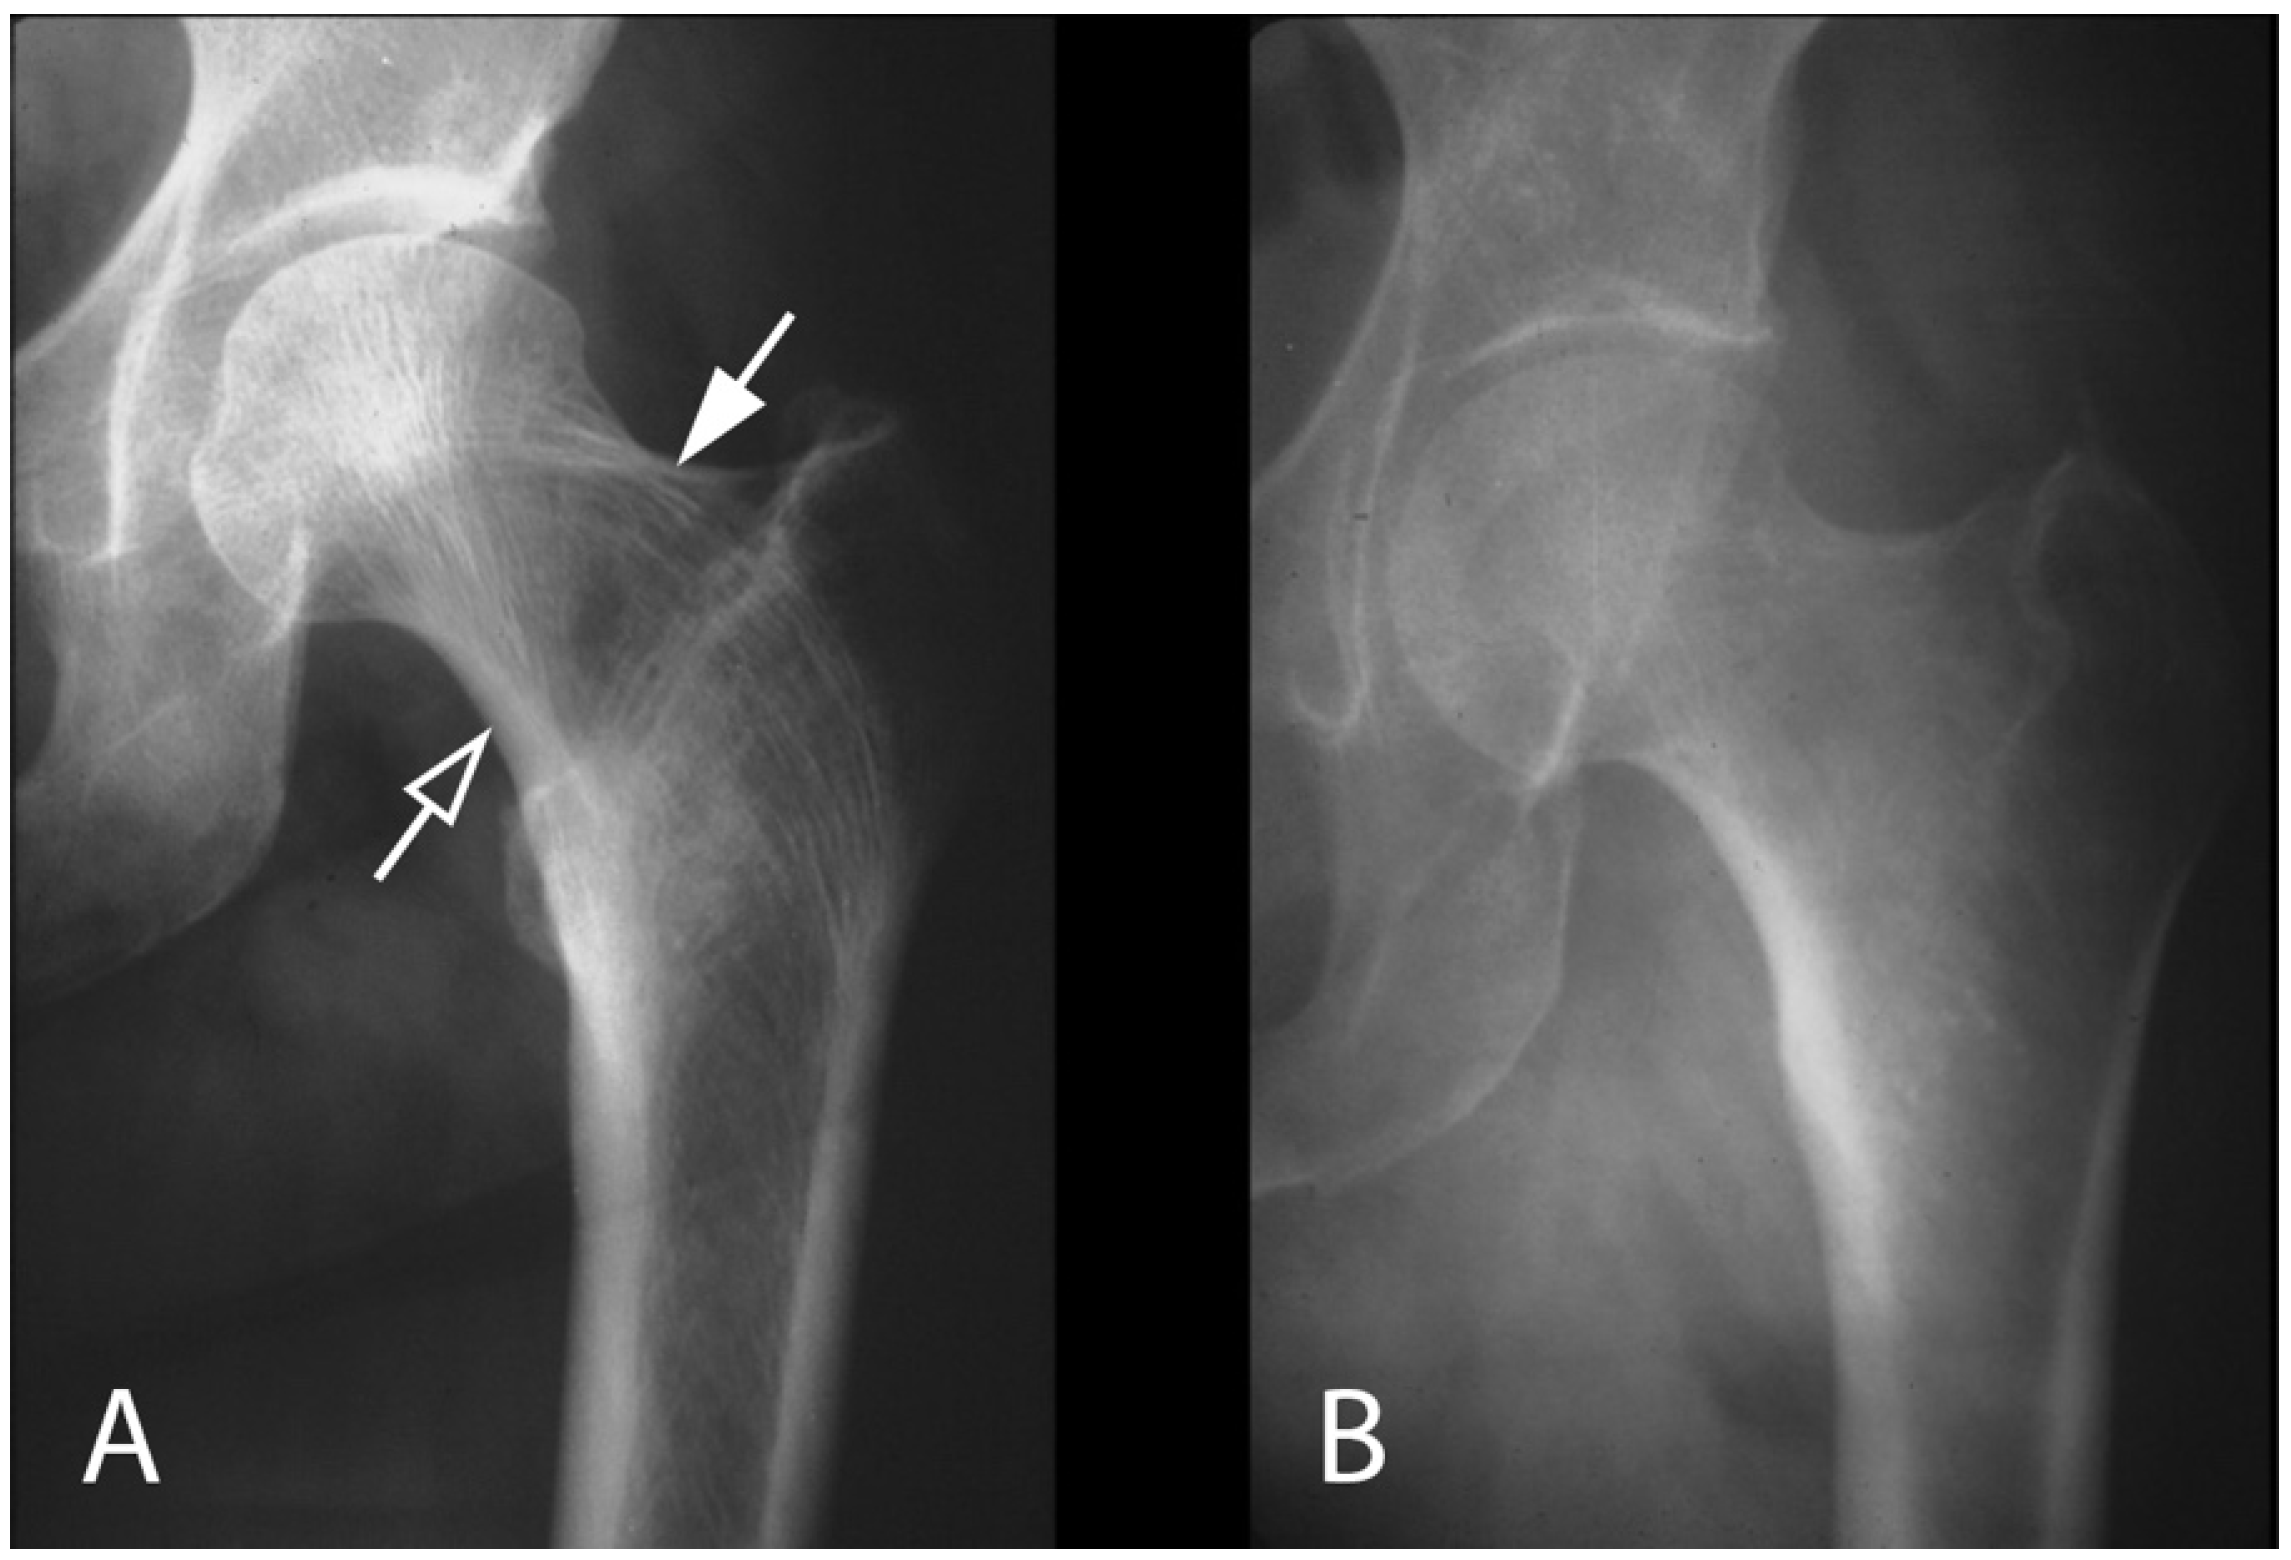

4.2. Bone Pathology of Fibrous Dysplasia

- Palmisano, B.; Spica, E.; Remoli, C.; Labella, R.; Di Filippo, A.; Donsante, S.; Bini, F.; Raimondo, D.; Marinozzi, F.; Boyde, A.; et al. RANKL Inhibition in Fibrous Dysplasia of Bone: A Preclinical Study in a Mouse Model of the Human Disease. J. Bone Miner. Res. 2019, 34, 2171–2182. [Google Scholar] [CrossRef]